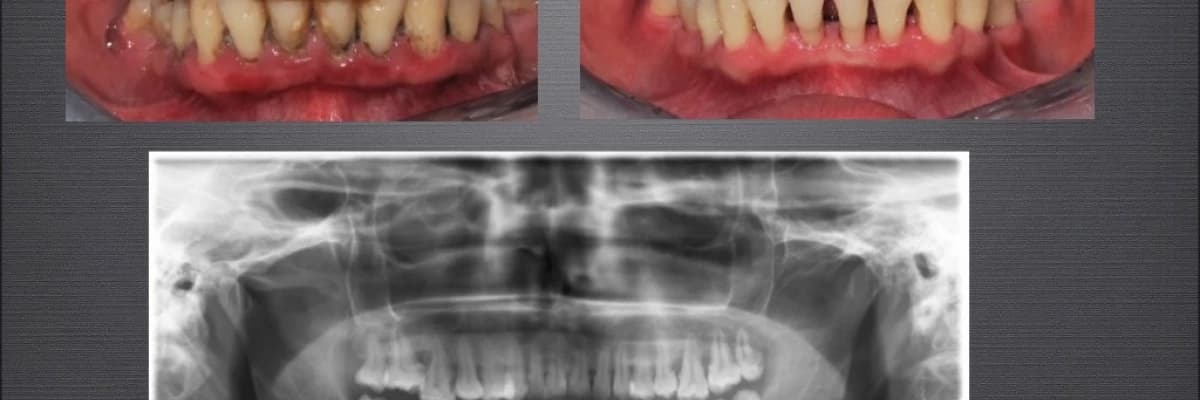

Dişeti hastalıkları iltihabi hastalıklardır ve tedavi edilmediğinde yıllar içinde diş kayıpları görülür. Dişeti hastalığı birkaç diş üzerinde lokalize gelişebilir yada bütün ağzı kapsayabilir. Dişeti hastalıkları genellikle başlangıç seviyesinde semptomsuz ilerleyen hastalıklardır. Orta ve ileri aşamalarda ise semptomlar görülmeye başlanır. Bunlar;

Dişeti hastalığının birincil sebebi bakterilerdir. Özellikle hastalık yapıcı bakterilerin diş ve dişeti arasında birikimi ile hastalığın belirtileri görülmektedir. Tedavi edilmez ise dişi çevreleyen kemik dokusunda erimeler görülmeye başlanır. Dişetinde de yapısal değişiklikler görülebilir (renk, şekil, hacim değişikliği gibi). Dişetinde meydana gelen bu iltihabi durumlar hastanın varolan sistemik rahatsızılıklarını da olumsuz yönde etkileyebilir. Diabet hastası bir hastanın kan şeker seviyesinin dengelenmesi zor olabilir. Kalp damar hastalıklarının olması da iltihapla etkilenebilir.

DİŞETİ TEDAVİ AŞAMALARI

Başlangıç Dişeti Tedavisi:

Diştaşlarının temizliği, diş kök yüzeylerinin düzeltilmesi ve hastaya uygun ağız bakımının planlanmasını içeririr. Bir veya birkaç seans sürebilir. Bu tedavilerin yeterli olmadığı durumlarda daha ileri cerrahi tedaviler planlanır.